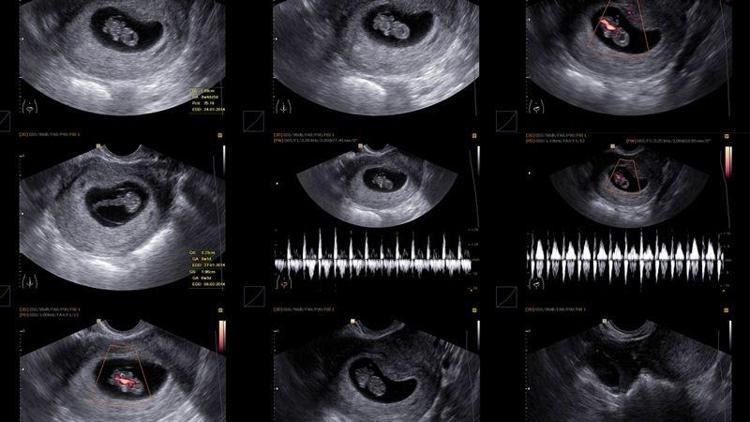

Ultrasonda gebelik kesesi kaçıncı haftada görülür? Boş kese gebelik nedir? Gebelik kesesi ne zaman belli olur? Vajinal ultrasonda gebelik kesesi ne zaman görülür? Gebelik kesesi kaç mm olunca bebek görünür?

Ultrasonda gebelik kesesi gebeliğin 5. veya 6.haftasında görülmesi mümkündür. Gebelik kesesi, bebeğe dair ultrasonda ilk görünen yapıdır. Gebelik kesesi en erken kanda beta hCG değeri 1000-3000 IU/mL düzeyine ulaştığında görülebilir. "

Ultrason muayenesi karından ve vajinadan olmak üzere iki farklı şekilde yapılır. Abdominal yoldan yapılan ultrasonografide gebelik kesesi yaklaşık 1 hafta daha geç görülebilir.

Gebelik kesesi 4.5-5. haftalarda vajinal ultrason ile görülebilmekte iken 6. haftalarda da kesin olarak karından görülmesi gerekmektedir. Gebelik kesesinin çapının transvajinal ultrasonografide 10 milimetreye ulaştığında yolk kesesi izlenmelidir. Bu oluşumun izlenmesi gebeliğin normal olduğu şeklinde yorumlanır.

Gebelik kesesi, 3 haftalık iken çapı ortalama 2-3 mm kadardır. Gebelik 5-5.5 haftalık olduğunda kesenin çapı ortalama 20 mm’ye ulaşır. Ayrıca gebelik kesesinin içinde yolk kesesi adı verilen kese görülmeye başlar. Bu kesinin varlığı, gebeliğin boş gebelik olmadığını doğrular.